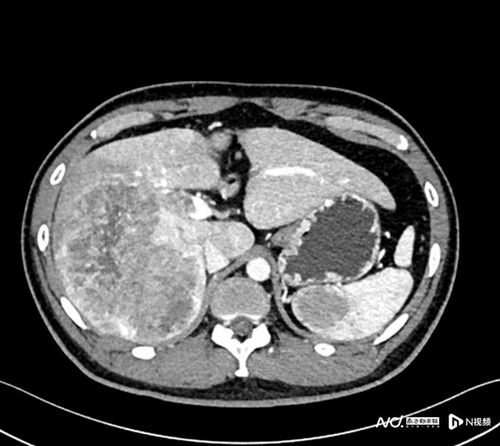

筛查癌症的化验什么(癌症筛查)

癌症筛查:从化验到影像的全面解读 癌症筛查,作为预防与早期发现癌症的关键手段,其化验项目丰富多样,既有血液检查中的肿瘤标志物检测,又需结合影像学检查进...